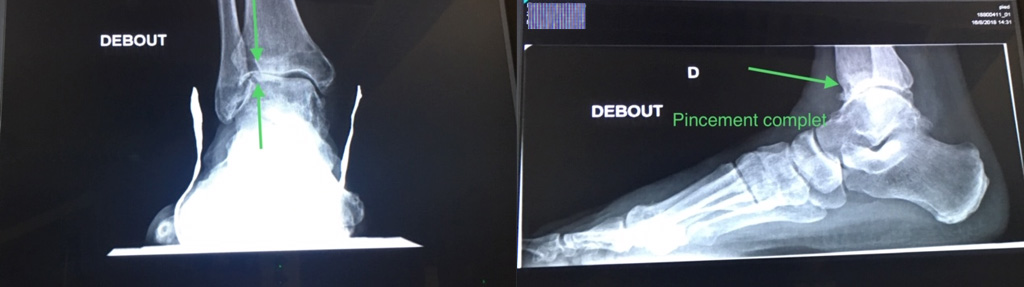

Le bilan doit comporter au minimum des radiographies de face et de profil en charge des deux chevilles. Ce bilan permet dans la plupart des cas de décider de l’option thérapeutique. Le scanner et l’arthroscanner sont demandés en seconde intention. Ils permettront de dépister les lésions associées, la qualité de l’os et la présence ou non de nécrose. A l’issue de ce premier bilan et si les critères cliniques et radiologiques de base orientent vers une indication d’arthroplastie (prothèse de cheville), un bilan complémentaire est indispensable et est requis pour introduire la demande de remboursement à l’INAMI. Il comportera :